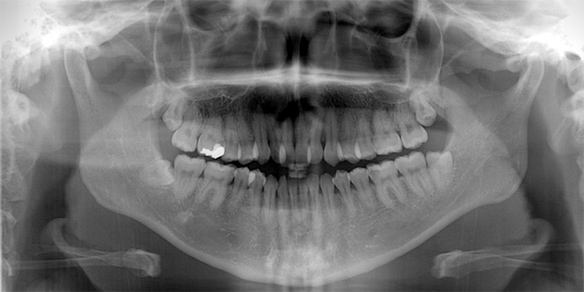

精密検査

矯正治療の前に、精密検査を行います。歯や顔の写真、歯や頭部のレントゲン写真、歯型の採取などを行い、現在の状態を正しく把握します。症状に応じて顔面形態、顎の関節など細かい部分の検査、分析も行います。

レントゲン写真を元に、

歯並びと

顎骨の分析をします

矯正カウンセリングにこられた方へ、WEBCEF(ウェブセフ)よる歯列矯正の解析レポートを作成し、詳しいご説明の上でご提供します。

精密検査料

パノラマレントゲン・セファロ矯正レントゲン・写真撮影の費用分析したデータを基に診断を行い、次回に診断結果をご説明します。